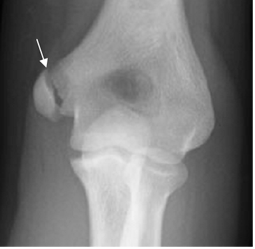

Fig 37 B. Avulsión del codo.

Rx AP. Desplazamiento inferior del núcleo de crecimiento, del epicóndilo medial.